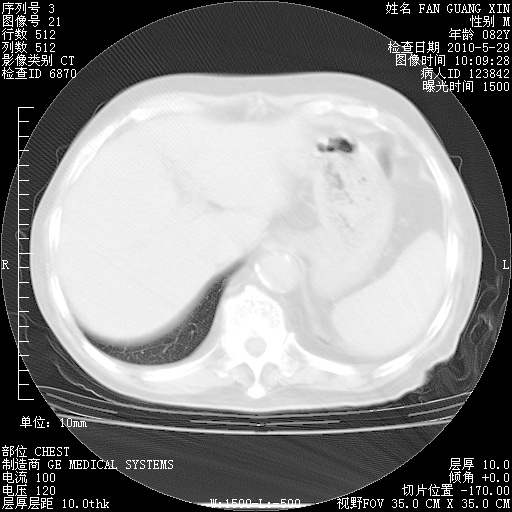

再治疗10天后的肺部CT

阅读此次胸部CT,肺间质渗出性改变较入院时有吸收。目前从体温、白细胞、中性分叶明显增高,肯定存在细菌感染(发生医院感染哦,若无消化道及泌尿系统等感染的依据,肺部感染可能大)。若你院头孢哌酮舒巴坦钠耐药率较高,同意你的方案,若48小时体温仍高,可考虑使用碳青霉稀类抗菌药物,同时可予超声雾化、注意滴数时加大液体量。白蛋白33.30g/L较低哦,需加强营养等支持治疗。